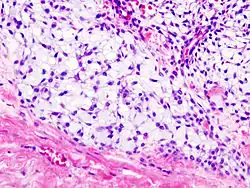

Histopathology

Imaging studies - including radiographs ("x-rays"), computerized tomography (CT), and magnetic resonance imaging (MRI) - are often used to make a presumptive diagnosis of chondrosarcoma.[11] However, a definitive diagnosis depends on the identification of malignant cancer cells producing cartilage in a biopsy specimen that has been examined by a pathologist. In a few cases, usually of highly anaplastic tumors, immunohistochemistry (IHC) is required.

There are no blood tests currently available to enable an oncologist to render a diagnosis of chondrosarcoma. The most characteristic imaging findings are usually obtained with CT.